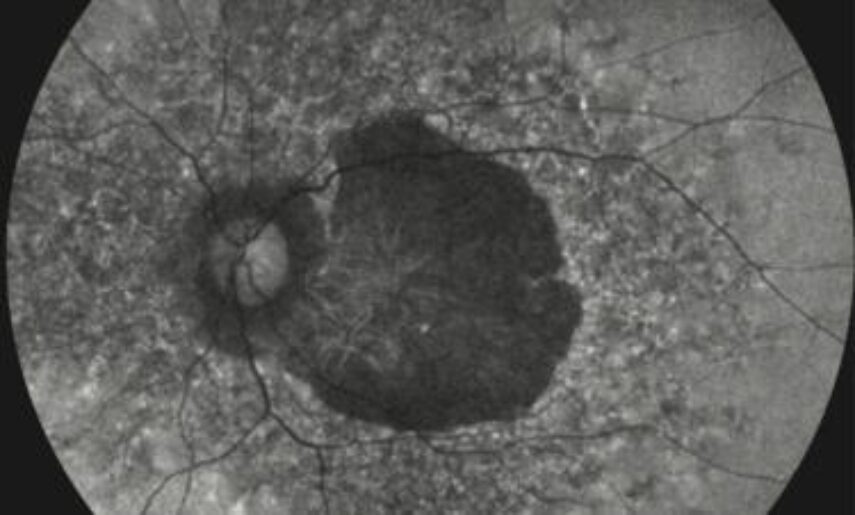

In this study published in the American Journal of Human Genetics (AJHG), they examined 22 affected individuals from 19 unrelated families, all of whom exhibited a consistent pattern of macular degeneration, the deterioration of the central part of the retina responsible for sharp, detailed vision.

Based on these findings, the researchers propose classifying this condition as “lysosomal macular dystrophy”, highlighting its connection to lysosomal storage diseases and providing a framework for future research and clinical management.